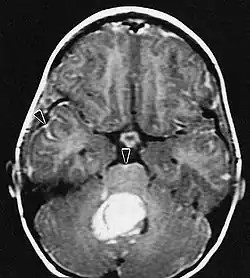

Na -MRI ukazuje intrakraniální tumor jako masivní lézi, která se po použití kontrastní látky může stát více luminiscenční. Vždy však dojde k anomálii signálu -Magnetická rezonance, která indikuje přítomnost neoplazie nebo vazogenního edému. Obvykle zvýšená luminiscence (zesílení kontrastu) svědčí pro nádor vyššího stupně malignity. Pro glioblastom je charakteristický kontrastní prstenec, jehož luminiscenční část odpovídá vitální části maligního nádoru a tmavší -hypointense oblast odpovídající nekróze tkáně.

Pacienti trpí řadou charakteristických symptomů fokální nebo multifokální masivní léze. MRI obvykle ukazuje nádory s homogenním zvýšením kontrastu v hluboké periventrikulární bílé hmotě. Pro pacienty s oslabeným imunitním systémem je typická multifokalita a nehomogenní zesílení. Analýza lymfomu CNS je mimořádně důležitá v diferenciální diagnostice neoplazie mozku. Je třeba poznamenat, že podávání kortikosteroidů může vést k úplnému vymizení zesílení, což ztěžuje diagnostiku lézí. V důsledku toho, má-li být lymfom CNS zvažován v diferenciální diagnóze, je třeba se kortikosteroidům vyhnout, pokud hromadný účinek nezpůsobí u pacienta závažný a bezprostřední problém.

Mozkové metastázy jsou nejčastějšími intrakraniálními novotvary u dospělých, jsou desetkrát častější než primární mozkové nádory. Krokují na 20 do 40 procenta dospělých s rakovinou a jsou spojeny hlavně s rakovinou plic a prsu a melanomem. Tyto léze jsou výsledkem šíření rakovinných buněk krevním řečištěm a nejčastěji se vyskytují na křižovatce šedé a bílé hmoty, kde se mění průřez krevních cév a zachycují embolie nádorových buněk. 80 procento lézí se vyskytuje v mozkových hemisférách, 15 procenta v mozečku a 5 procent v mozkovém kmeni. Asi 80 procento pacientů má v anamnéze systémovou rakovinu a 70 procento má četné mozkové metastázy.